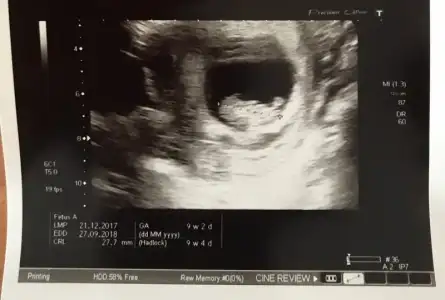

D4854C9D-3D23-4E23-A298-AA0477D440E3.webp Kızlar kontrolden geldim. Çok şükür yolunda görünüyor herşey. 9+2 yiz ama 9+4 ölçtü doktor :) cinsiyet tahmini yapabilecek olan var mı ? :anneadayı::KK28:

Eki Görüntüle 2115455 Kızlar kontrolden geldim. Çok şükür yolunda görünüyor herşey. 9+2 yiz ama 9+4 ölçtü doktor :) cinsiyet tahmini yapabilecek olan var mı ? :anneadayı::KK28: